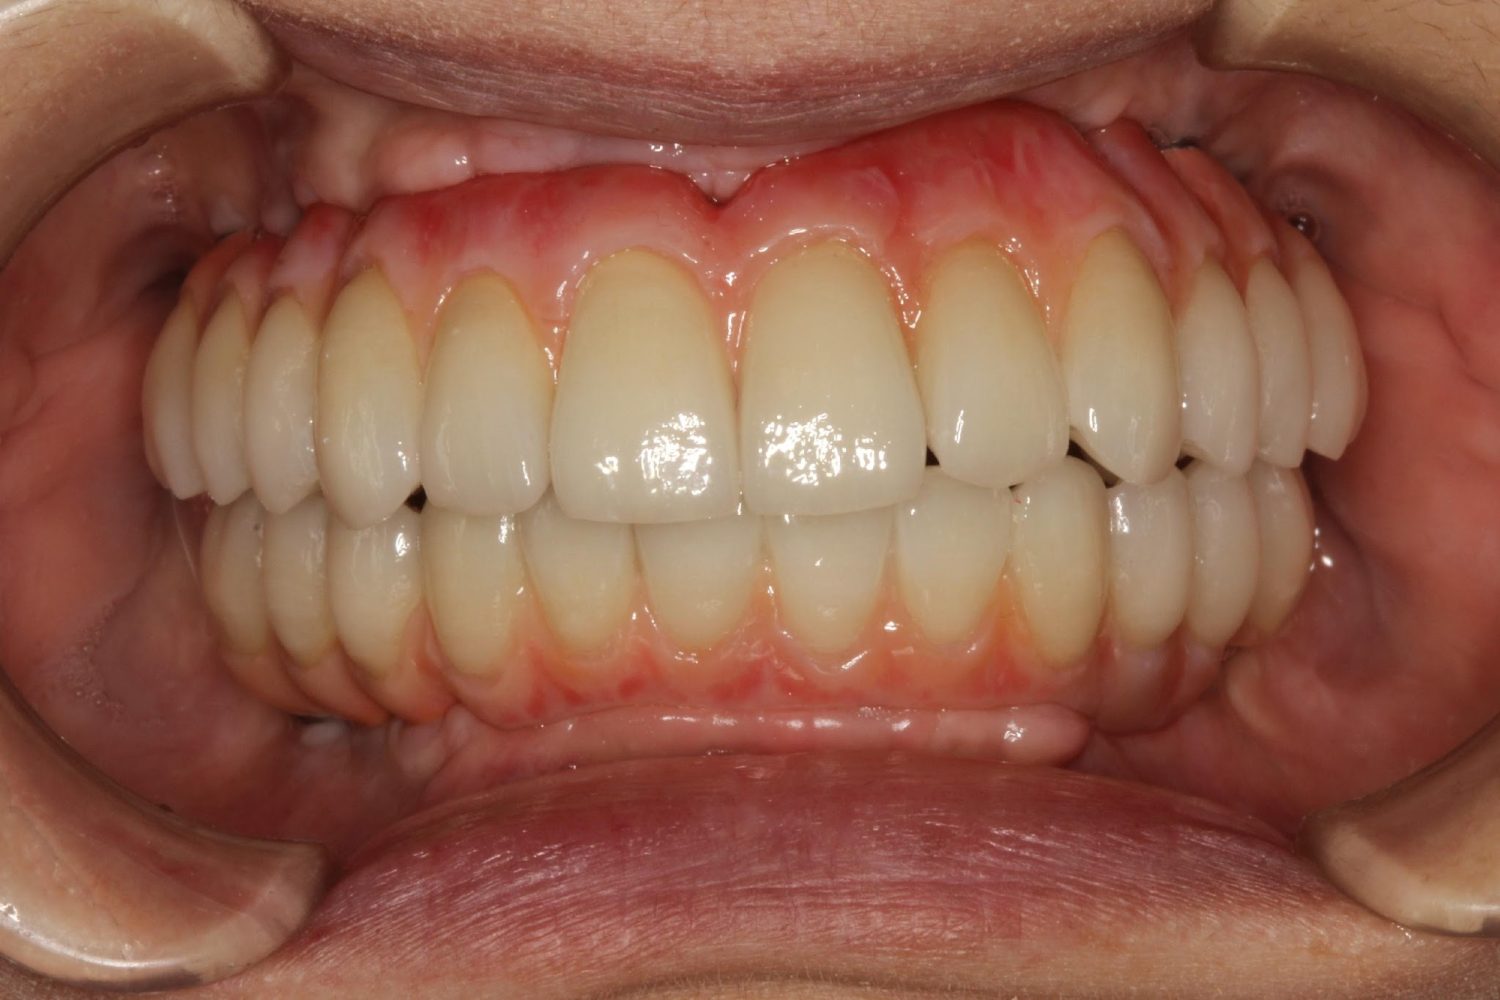

インプラント治療の症例紹介⑤

Before

After

主訴

歯肉腫脹、咬めるようにしたい

治療内容

重度歯周病により全ての残存歯保存不可能な状態。上下顎ボーンアンカードブリッジによる咬合再構成。

治療費

12,621,400円(税込)

治療期間

22ヶ月

通院回数

28回

想定されたリスク

※上部構造の形態が複雑になるため清掃が難しくなる、インプラント周囲炎の恐れがありました。

濱 仁隆先生

浜歯科

上顎8本下顎7本のインプラント体埋入によるボーンアンカードブリッジ。